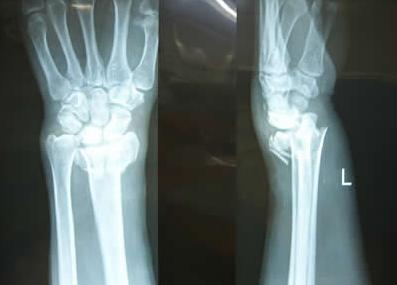

2.骨折线的高度。骨折线愈靠近股骨头愈高,坏死率愈高。根据骨折线部位可将股骨颈骨折分为头型、头下型、颈中型和基底型。>>>将我的片子给医生看下,请医生为我诊断

3.骨折断端原始移位程度。骨折断端原始移位严重者,发生股骨头坏死的机率极高。按骨折后Linton's角大小,将股骨颈骨折分为外展型骨折和内收型骨折。外展型骨折常属于无移位的线状骨折或移位很少的嵌插骨折,骨折比较稳定,关节囊破坏较少,愈合率较高,股骨头坏死较少,预后较好。内收型骨折断端及少嵌插,明显移位,属于不稳定性骨,远端因肌肉牵拉向上升,又因下肢重量而外旋,关节囊及血运破坏较大,愈合率比前者低,头坏死率高。